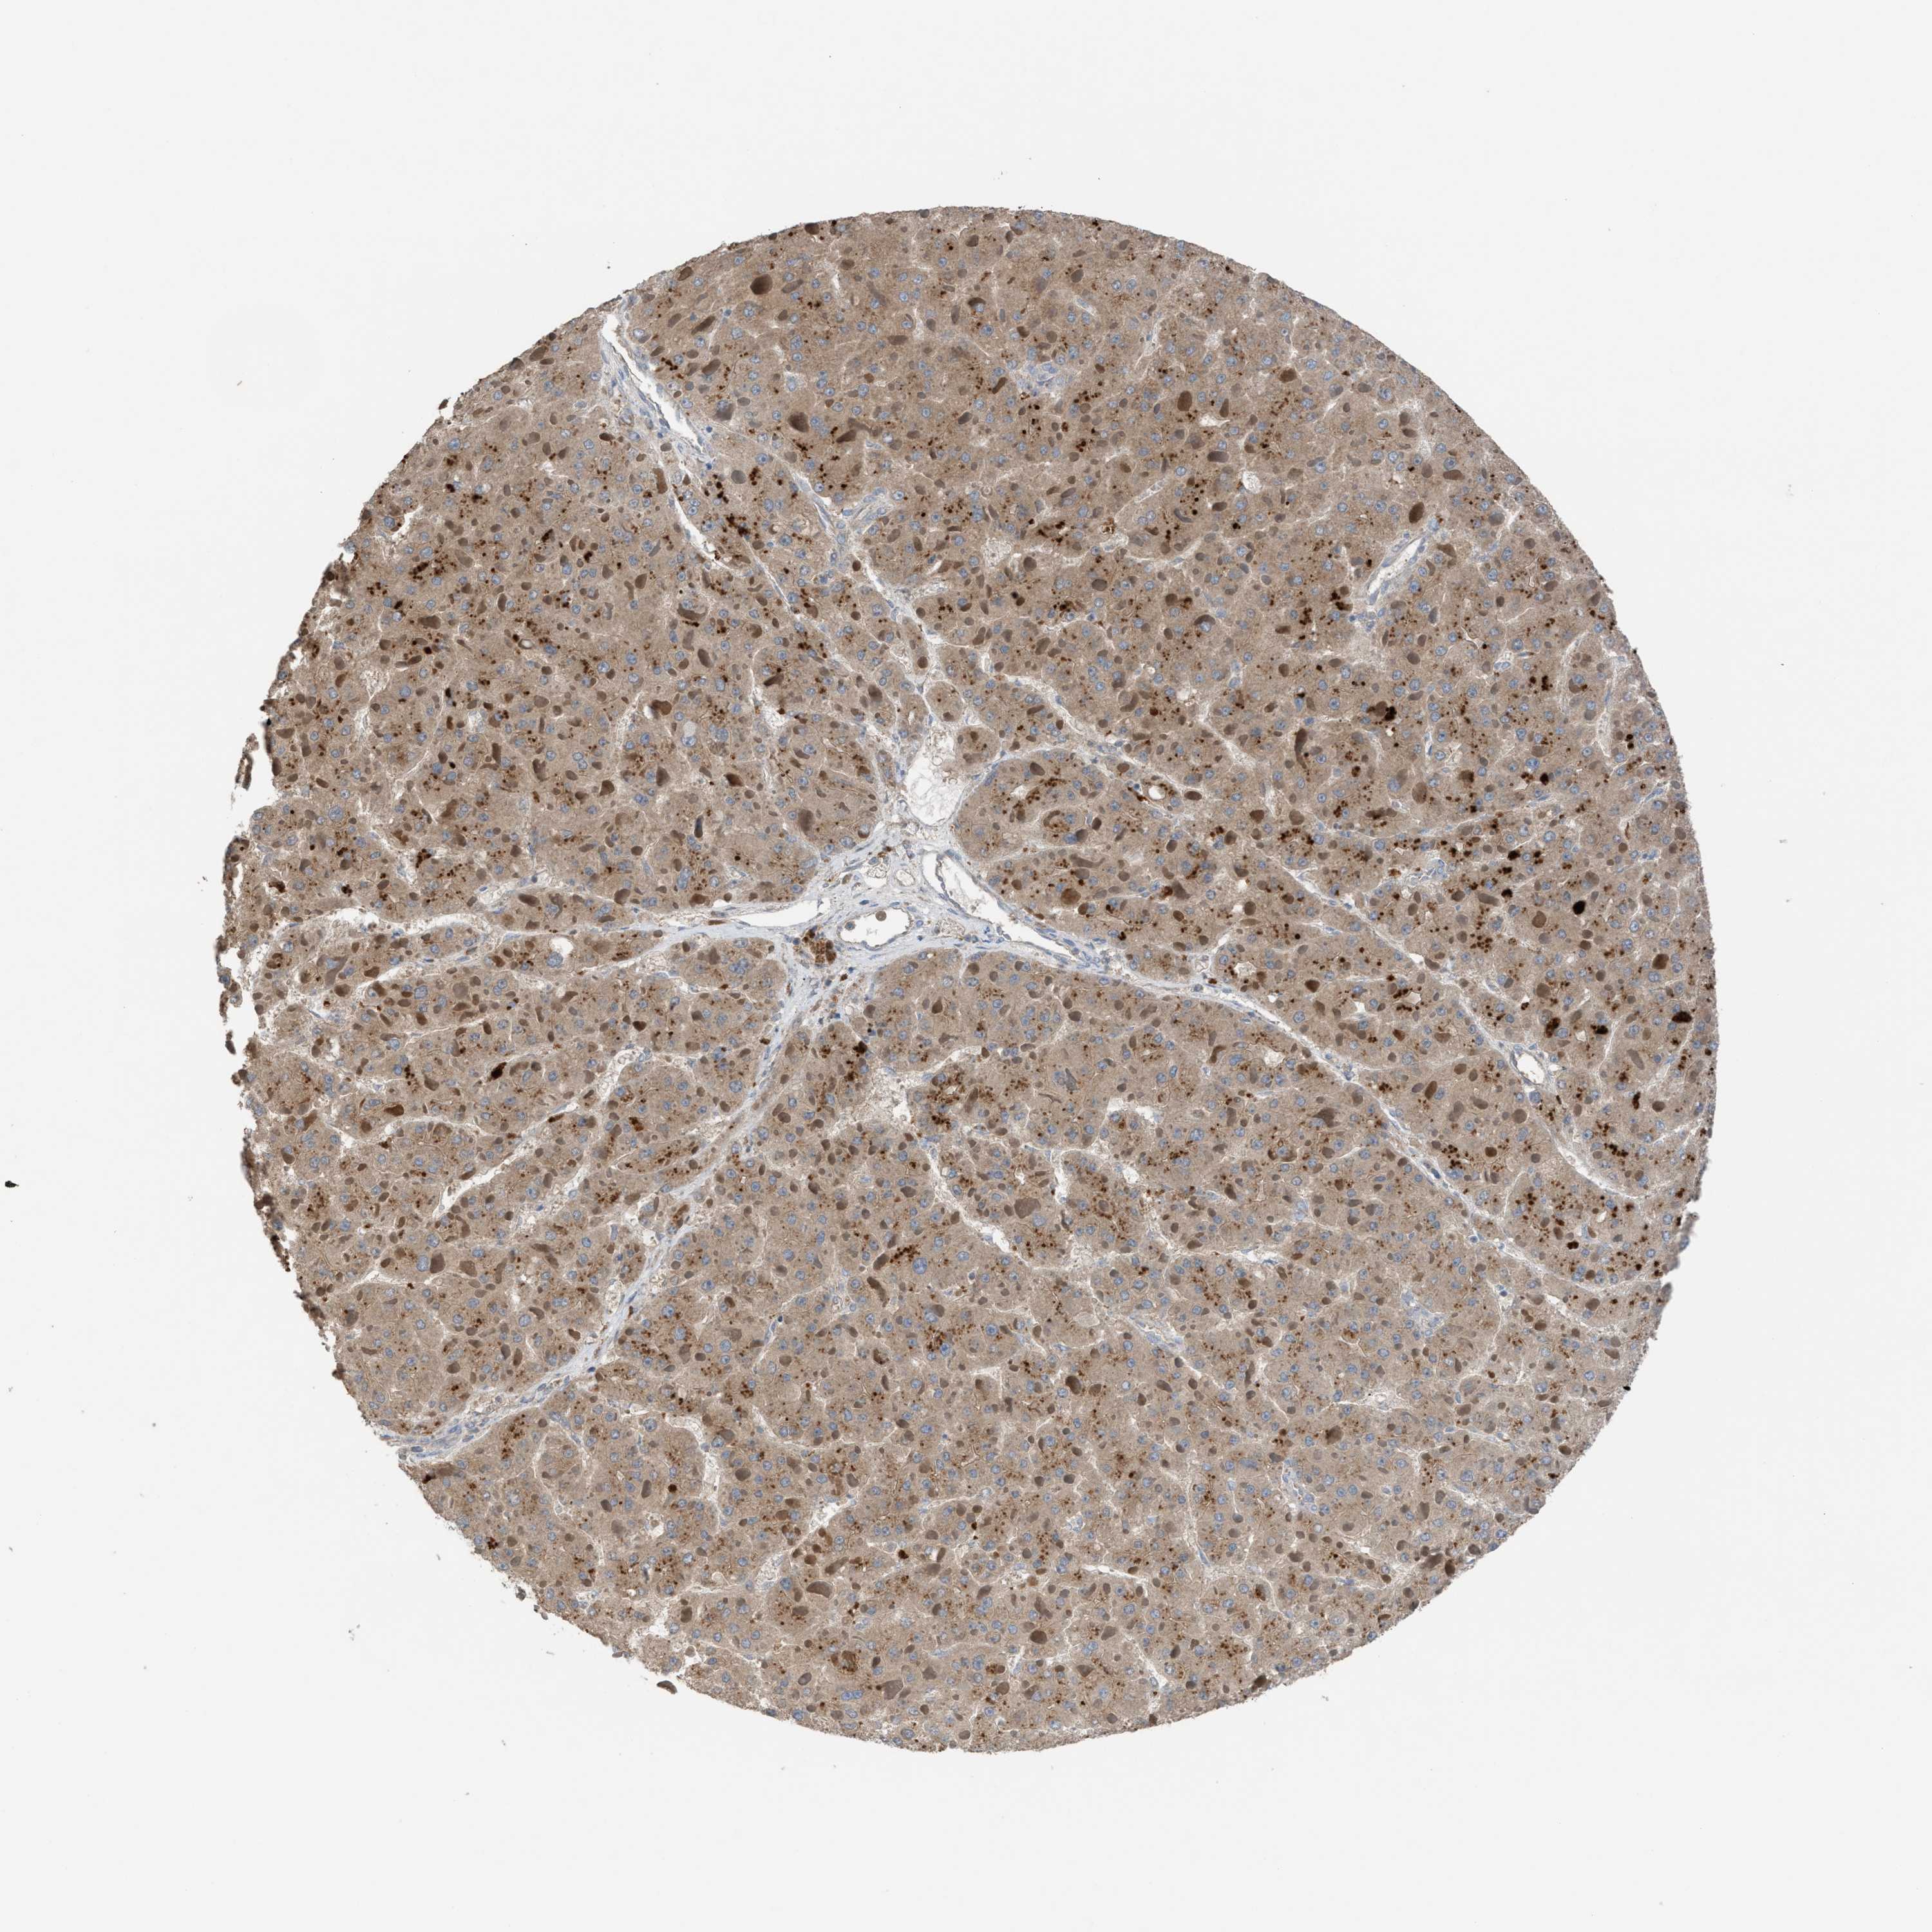

LIVER CANCER - Protein expressioni

A mouse-over function shows sample information and annotation data. Click on an image to view it in a full screen mode. Samples can be filtered based on level of antibody staining by selecting one or several of the following categories: high, medium, low and not detected. The assay and annotation is described here.

Antibody stainingi

Antibody staining in the annotated cell types in the current human tissue is reported as not detected, low, medium, or high, based on conventional immunohistochemistry profiling in selected tissues. This score is based on the combination of the staining intensity and fraction of stained cells.

Each image is clickable and will lead to virtual microscopy that enables deeper exploration of all samples and also displays staining intensity scores, fraction scores and subcellular localization as well as patient and tissue information for each sample.

Antibody HPA021545

Antibody HPA021849

Staining

High

Medium

Low

Not detected

Intensity

Strong

Moderate

Weak

Negative

Quantity

>75%

75%-25%

<25%

None

Location

Nuclear

Cytoplasmic/membranous

Cytoplasmic/membranous,nuclear

Cholangiocarcinoma

Carcinoma, Hepatocellular, NOS